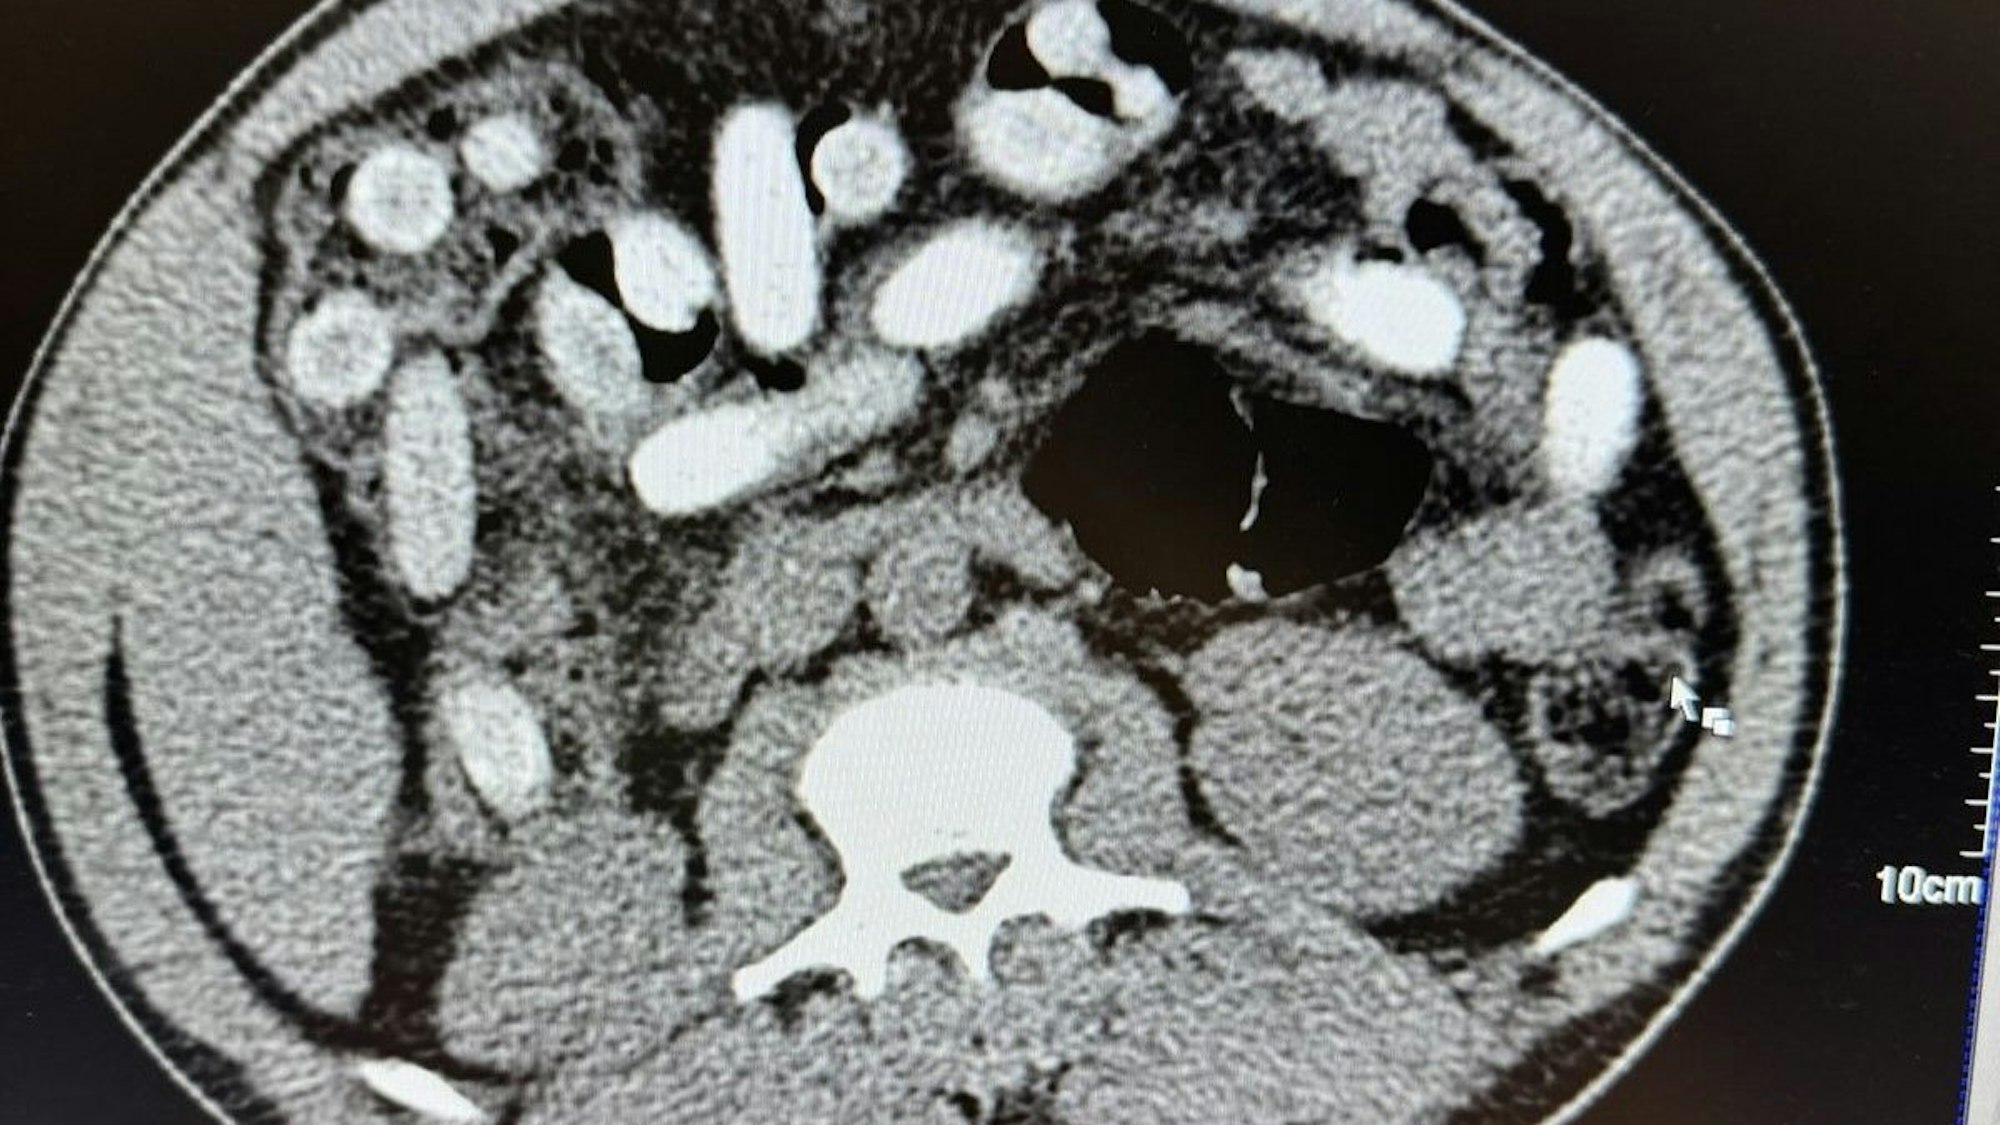

Die Polizei veranlasste ein Röntgenbild vom Magen des Verdächtigen.

Eine Röntgenaufnahme in einem Krankenhaus bestätigte den Verdacht. „Der komplette Magen-Darm-Trakt des Mannes war voll mit Drogenpäckchen, sogenannten Bodypacks. In der Größe und Form sind diese mit Datteln vergleichbar“, erklärte Jens Ahland, Pressesprecher des Hauptzollamts Köln.

Insgesamt habe der Mann 111 Päckchen mit rund 1,3 Kilogramm Kokain geschluckt. „Das Risiko beim Körperschmuggel ist enorm. Wenn nur ein Päckchen im Körper aufgeht, ist das Leben des Mannes nicht mehr zu retten“, so Ahland.

111 sogenannte Bodypacks mit Kokain haben die Beamten im Magen des Mannes gefunden.